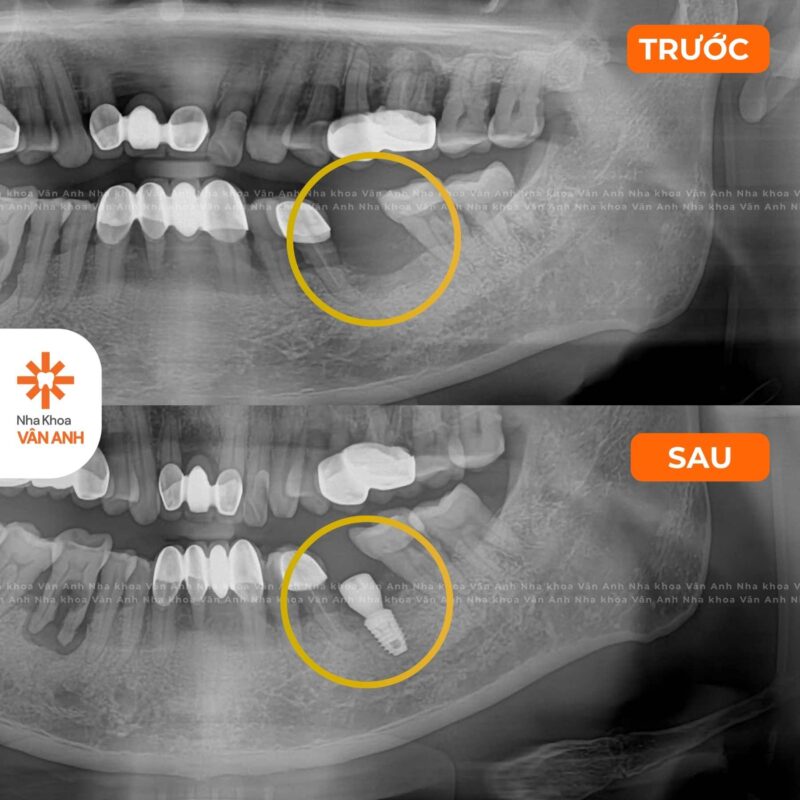

Lĩnh vực chuyên sâu: Phục hình – Tiểu Phẫu

- Chứng nhận Cấy ghép implant nha khoa cơ bản – Viện Đào tạo Răng Hàm Mặt, Đại học Y Hà Nội

- Chứng nhận Giải pháp ca nhổ răng khó – Implant cho xương xốp – Nâng xoang hạn chế ghép xương – Viện Đào tạo Răng Hàm Mặt, Đại học Y Hà Nội